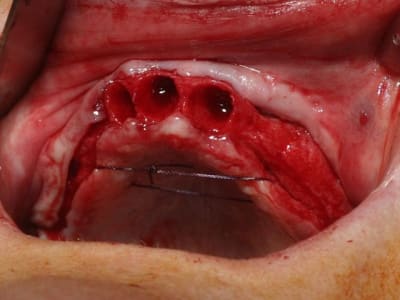

bon, toujours aussi speed je suis, mais après certaines réclamations, et malgrès ma réticence à poser un cas non "consolidé", voici en avant première mon premier all on 4, version photos ratées et non retouchées, mais... speed je suis je vous disais ;)

sto le bla bla, et pasons le diaporama... bon voyage au pays de la mise en charge immédiate totale au maxillaire de fille carole sur dame ginette, une patiente en or que j' adore, et pour qui je suis très très heureuse d' avoir pu réaliser cette chirurgie et la première étape prothétique.....

Tu as utilisé des Nobel Speedy si je ne me trompe pas.

Peux tu nous en dire un peu plus sur les implants, leurs diamétres et leur longueurs ?